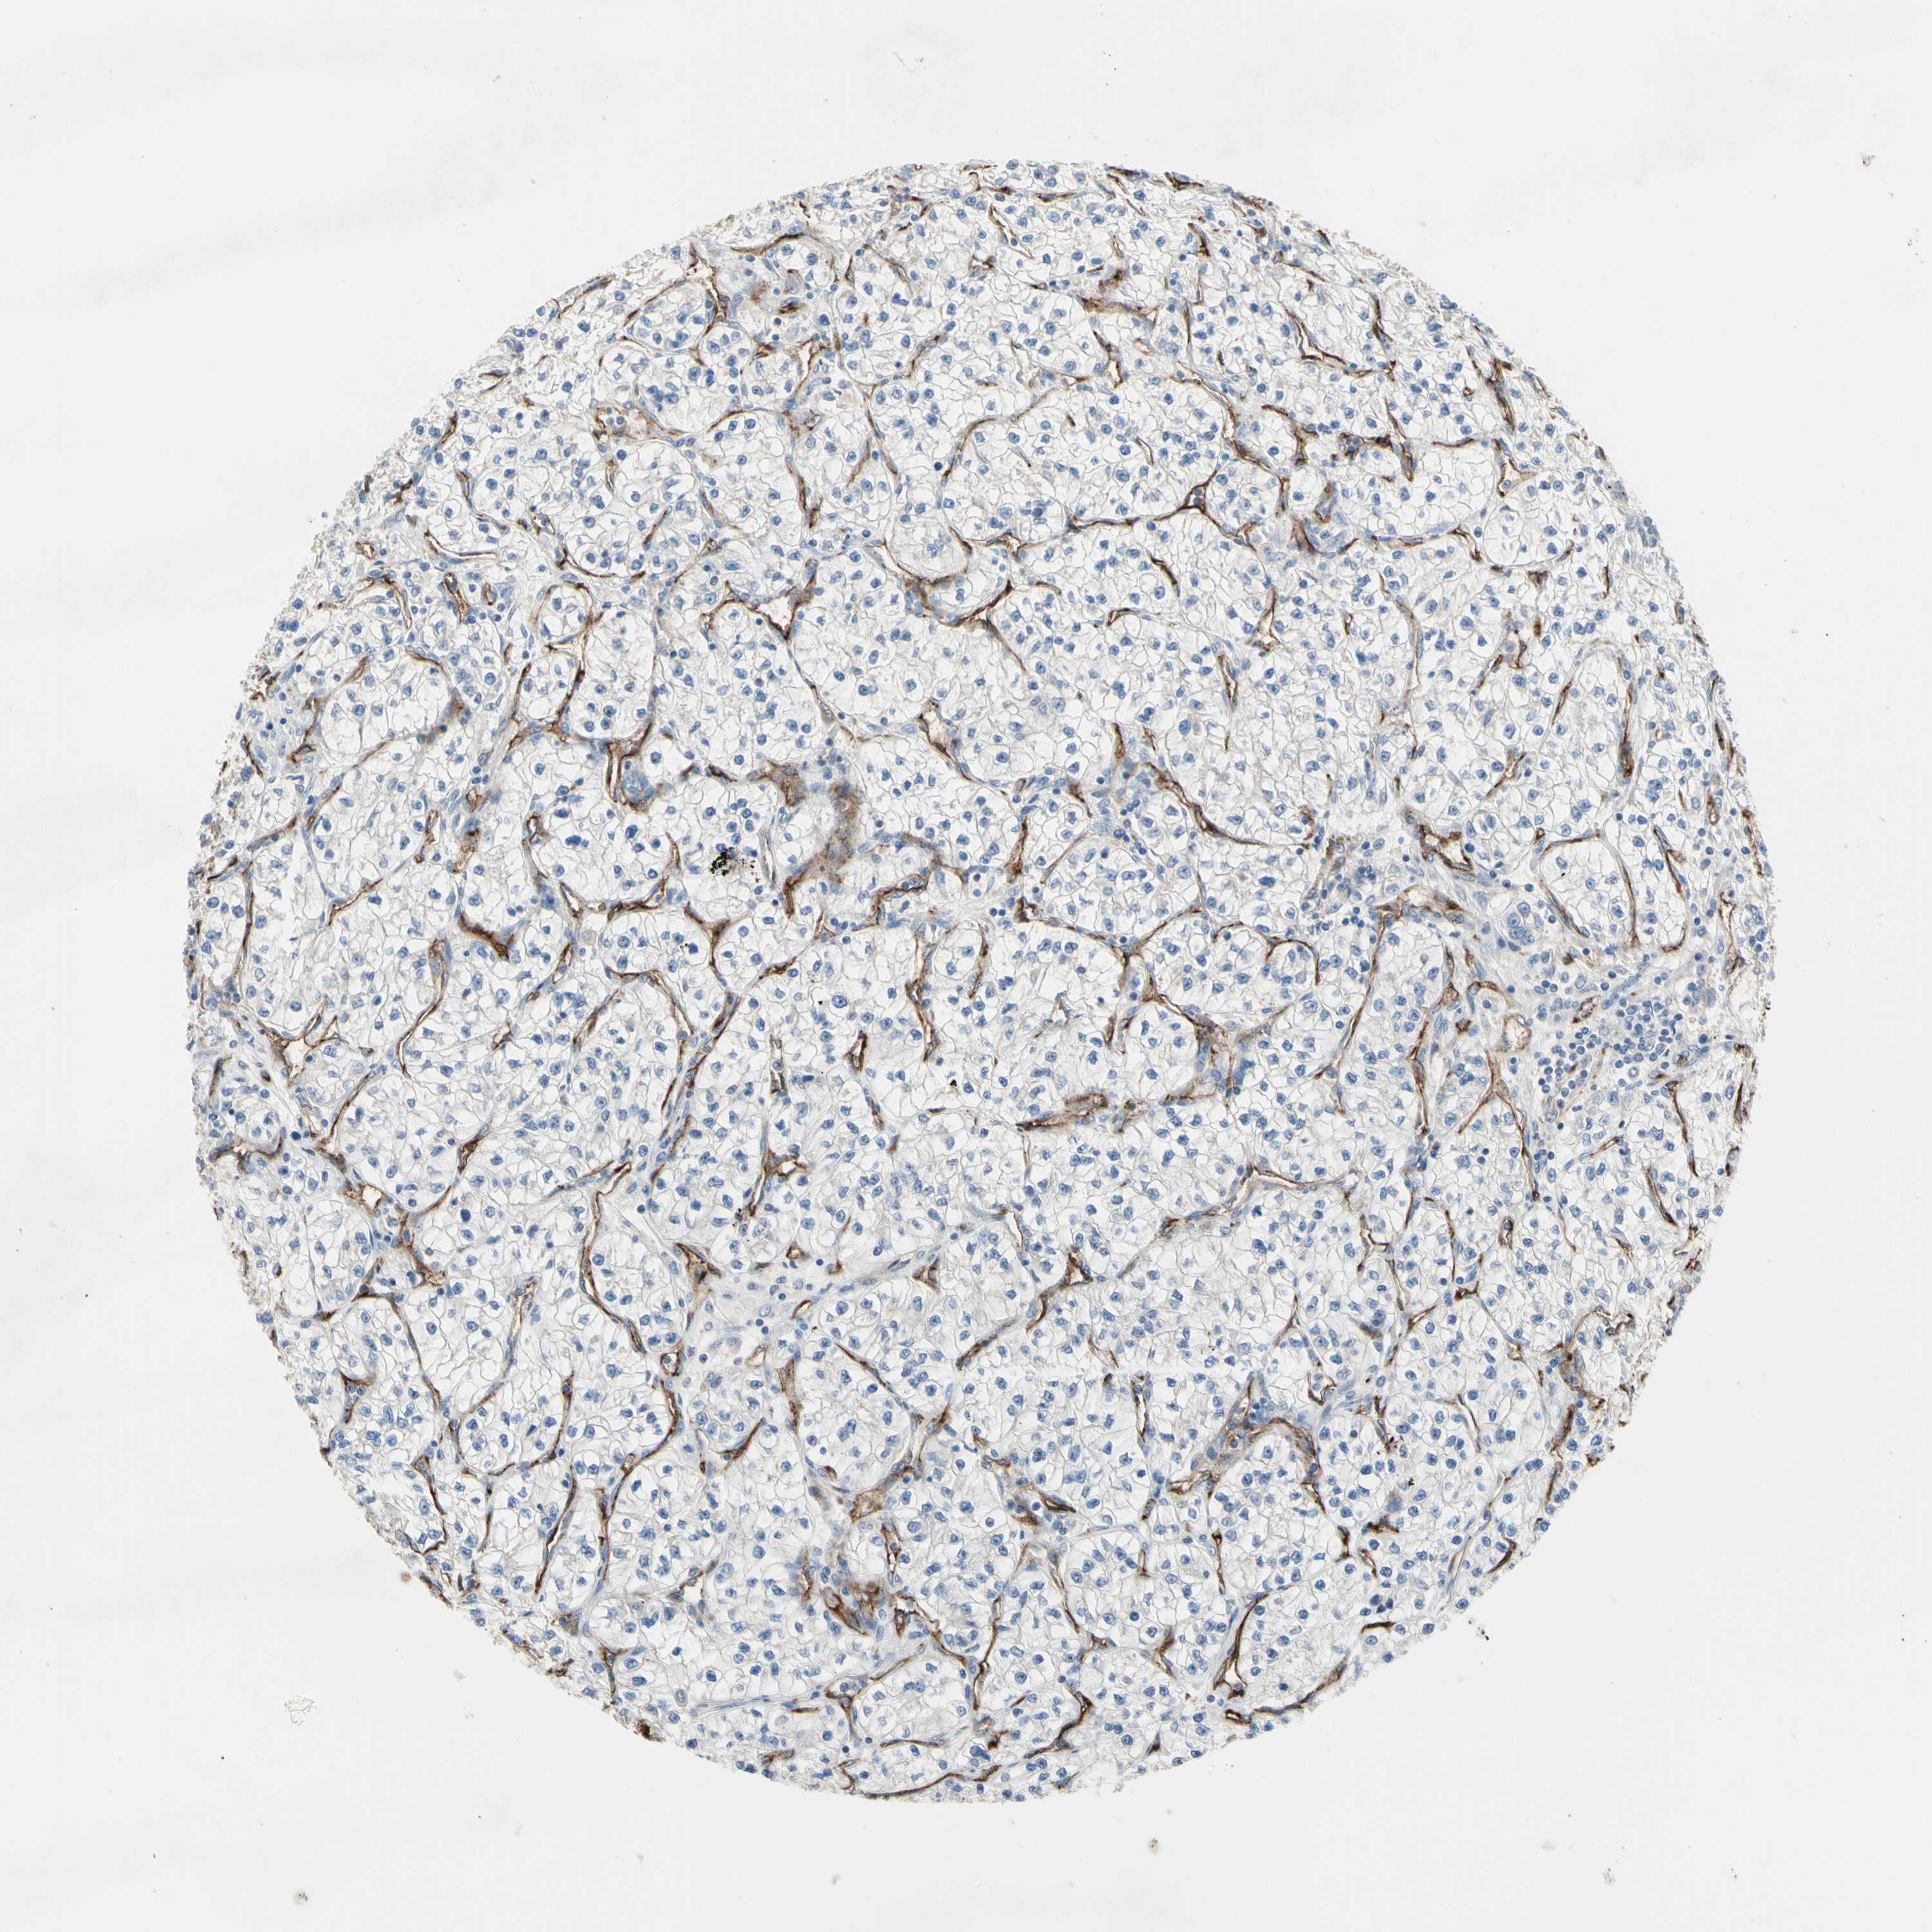

KIDNEY RENAL CLEAR CELL CARCINOMA (TCGA) - Interactive survival scatter ploti

TRAF2 is not prognostic in Kidney Renal Clear Cell Carcinoma (TCGA)

: 18

Average pTPM 15.3

Number of samples 521